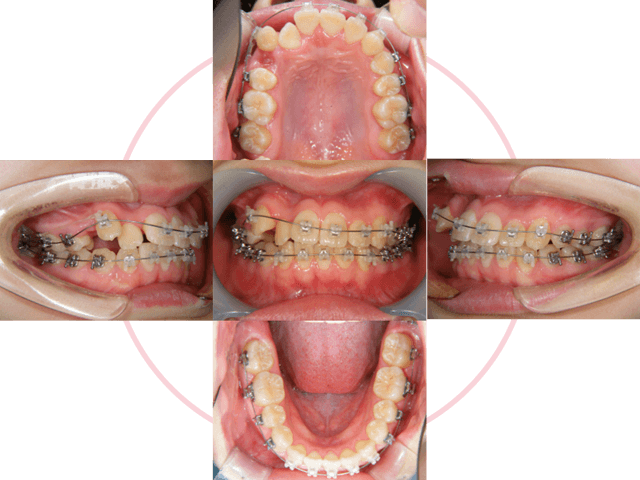

2

治療計画を立ててカウンセリング後、治療を開始します。ブラケットを歯に接着して、形状記憶合金のワイヤーを装着します。右上第一小臼歯を抜歯しています。